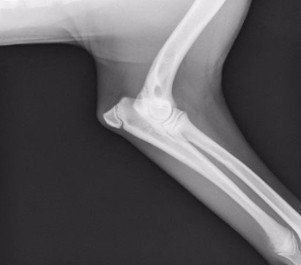

Displasia del gomito e neurologia veterinaria

Oltre all’anca, la nostra clinica si occupa anche della displasia del gomito, una patologia multifattoriale che colpisce spesso le razze di taglia grande. Essa può derivare da:

- frammentazione del processo coronoideo (FCP);

- mancata unione del processo anconeo (UAP);

- osteocondrite dissecante (OCD);

- incongruenza articolare (INC).